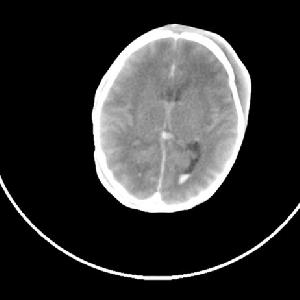

(3)其它:如動態觀察前囪及頭圍的變化,顱透照、頭顱B超及CT檢查等均可根據需要檢測。CT可精確了解病變類型、部位、出血程度,對預後做出估價,具體分度為:Ⅰ度:腦室管膜下出血;Ⅱ度:腦室出血不伴腦室擴張,以上90%存活;Ⅲ茺:腦室出血伴腦室擴張;Ⅳ充:腦室出血伴腦實質出血,其病死率50%。

⑤腦出血 包括原發性小腦出血腦室內或蛛網膜下腔出血擴散至小腦,靜脈出血性梗死,及產傷引起小腦撕裂4類型多見於胎齡小於32周、體重低於 1500g的早產兒,或有殘傷史的足月兒嚴重者除一般神經系統症狀外主要表現為腦幹症狀,如頻繁呼吸暫停、心動過緩等可在短時間內死亡,預後較差,尤其是早產兒。

顱內出血導致內分泌改變小腦幕下出血表現為腦幹受壓,呼吸循環障礙,病情較重,大腦出血表現為興奮尖叫、激惹和驚厥,硬腦膜下出血輕症可無症狀,重者可有偏癱、局限性抽搐,顱窩下血腫或小腦出血表現為延髓受壓,病情進展很快。